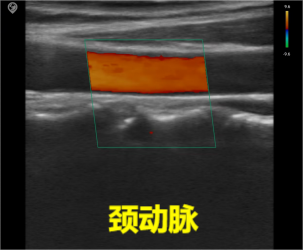

Common frequency range: 5.0MHz-16.0MHz,

Common scan width: 30-40mm,

Imaging depth: within 6cm from the skin.

Features: The probe surface is flat, with a large contact area, rectangular imaging field of view, high imaging resolution, and relatively low penetration depth; suitable for examination of superficial vessels, small organs, musculoskeletal structures, etc.